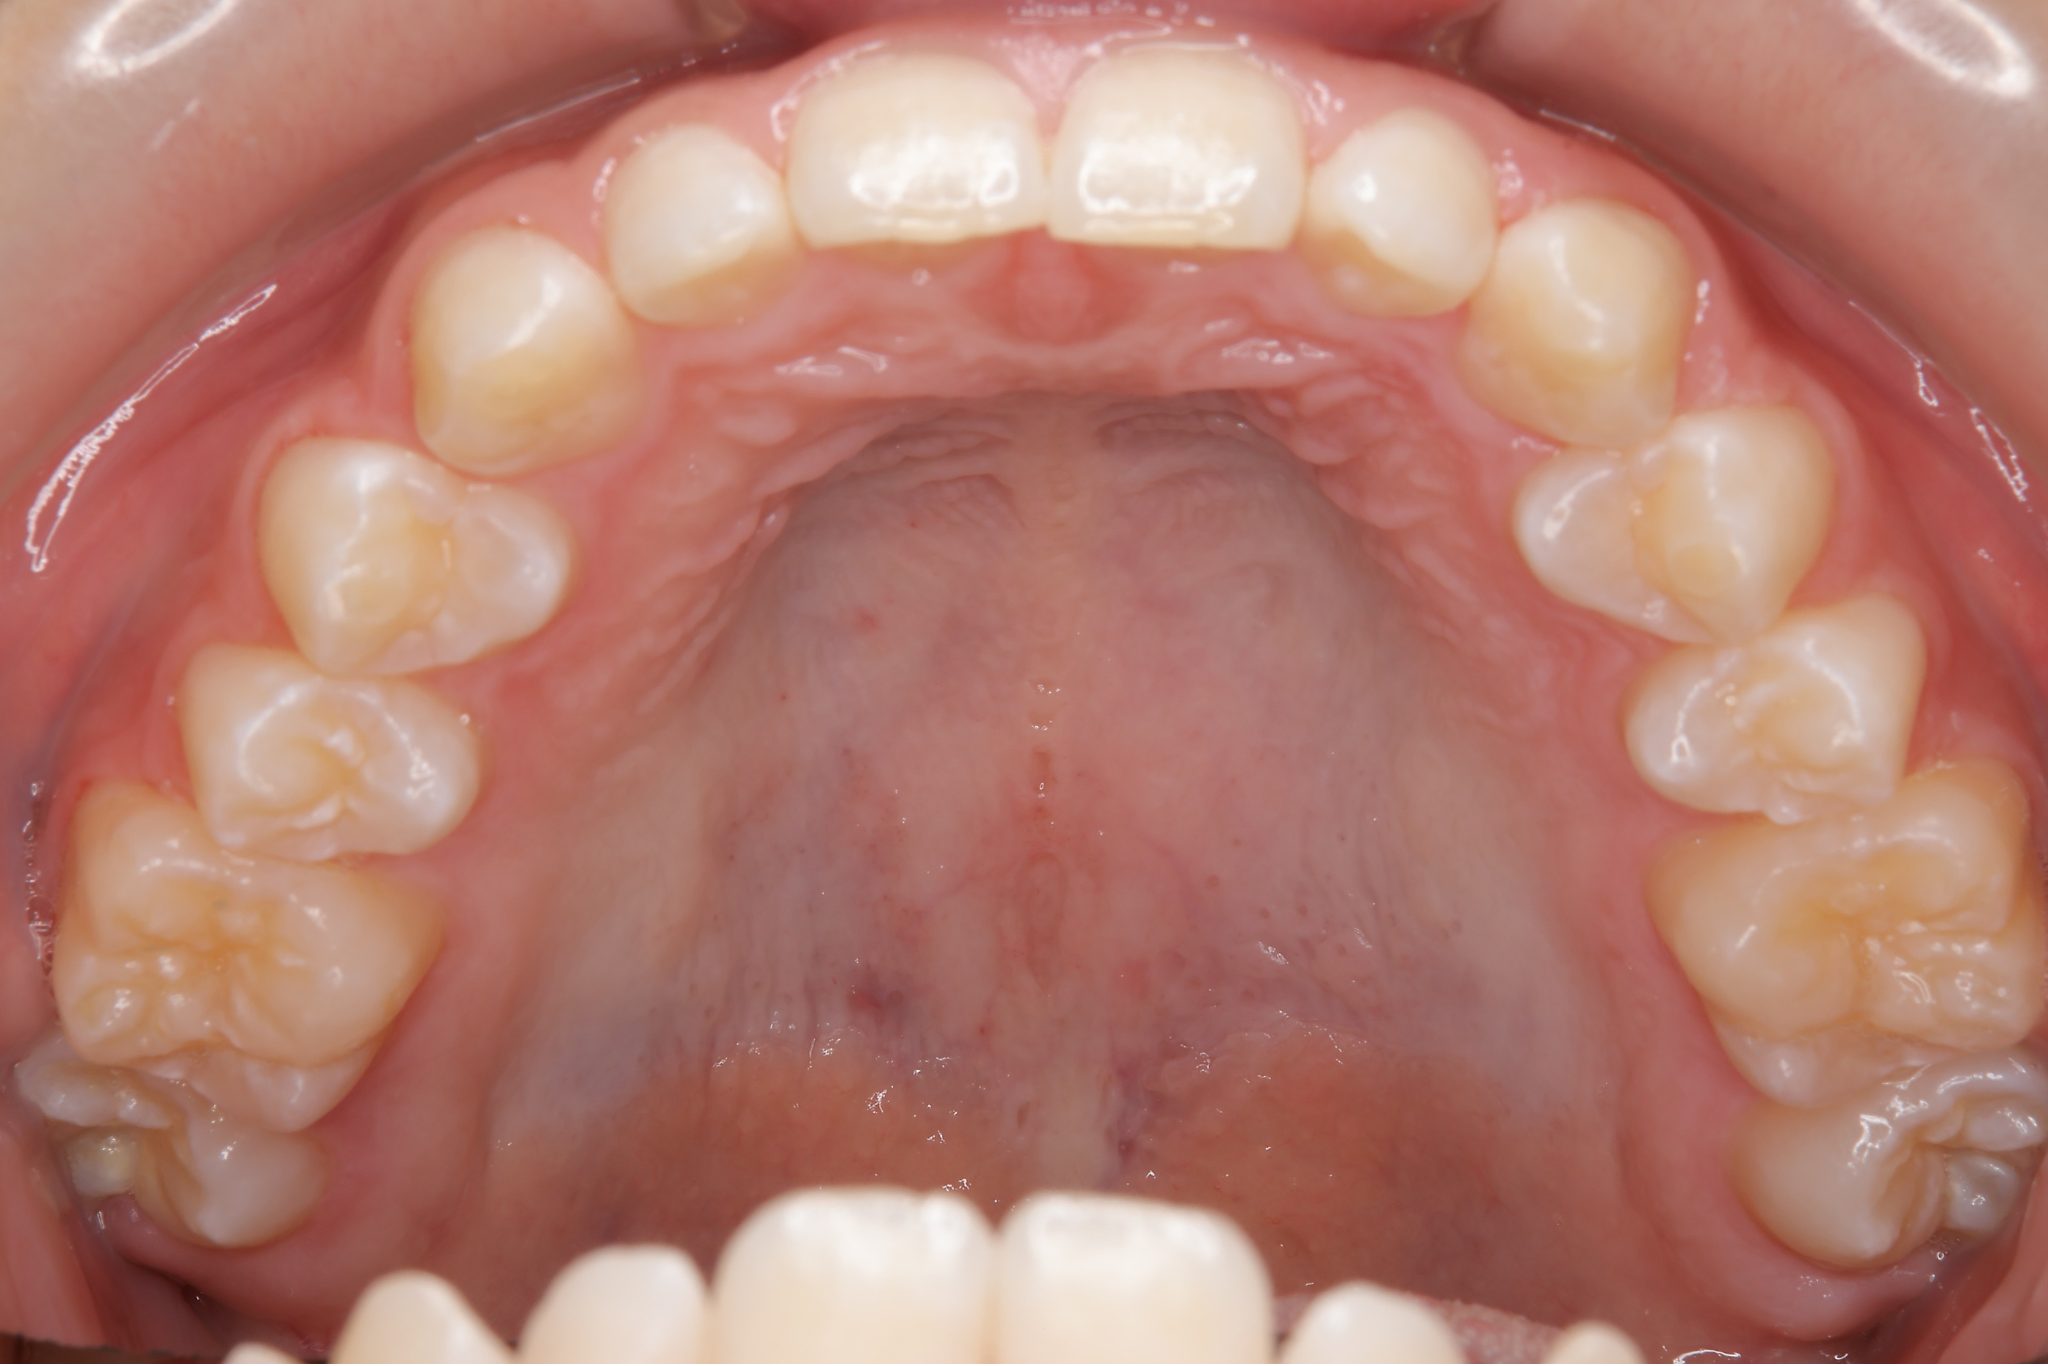

ビフォー

子どもの矯正治療|症例_121

主訴 歯並び

施術内容 上顎急速拡大装置と下顎リンガルアーチを用いて上下顎骨を拡大した。

その後マウスピース型矯正装置で歯牙を配列し良好な咬合を獲得した。

治癒期間 3年11ヶ月間